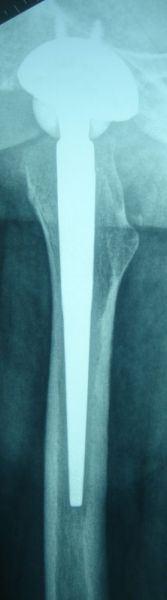

5. Periprosthetic fracture of the left femur in a 75-year-old male with a total knee arthroplasty.

Treatment: Open reduction internal fixation

I. Anteroposterior x-ray of the femur shows the periprosthetic fracture II. Post-surgery, x-ray shows the metal work and the reduction of the fracture. The arthroplasty was stable therefore there was no need in this stage for the replacement of the prothesis